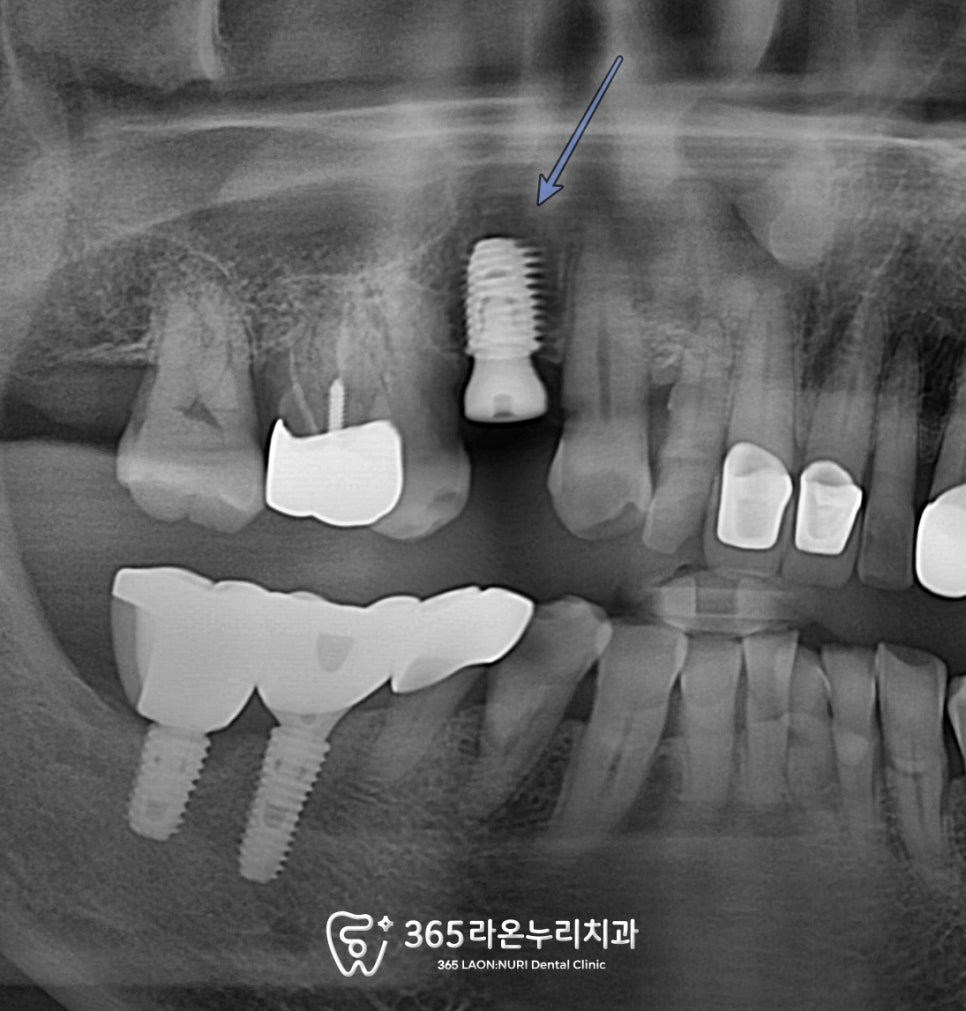

2025.4.28

식립 후 촬영한 파노라마를 남촌동 치과 에서

보면 미리 모의 식립을 진행한 덕분에

별 다른 문제 없이 안정적으로

식립에 성공한 모습을 볼 수 있었습니다.